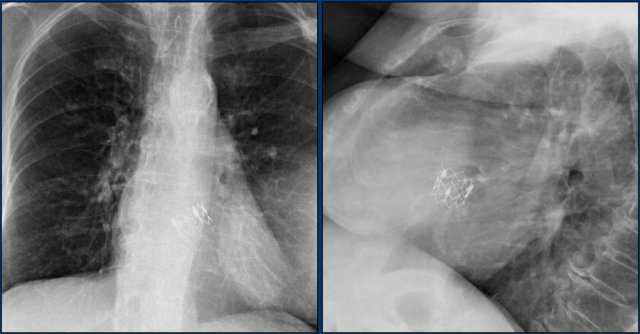

These are images of a patient with a persistent ductus arteriosus.

The ductus was closed with an Amplatz plug device.